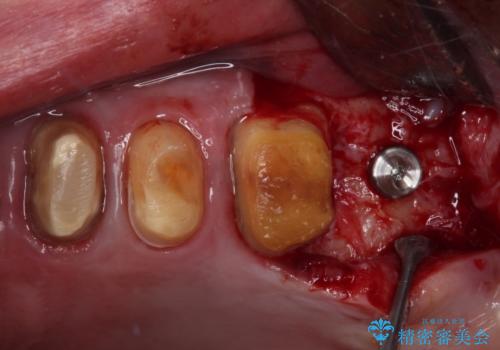

- 奥歯が咬みにくく、前歯がぐらぐらするとのことで来院された患者様です。

咬合力が強く、奥歯が欠損している状態でした。

欠損部はインプラントによる補綴治療を行うこととし、臼歯部が安定した後に、上下前歯部をオールセラミッククラウンにて補綴治療を行うこととしました。